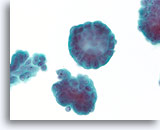

Papilloom, Borst FNA, Celblok.

Deze afbeelding van dezelfde FNA als in afbeelding 18 bevat een duidelijk papillaire architectuur.

Papilloom, Borst FNA, Celblok.

Deze afbeelding van dezelfde FNA als in afbeelding 18 bevat een duidelijk papillaire architectuur.